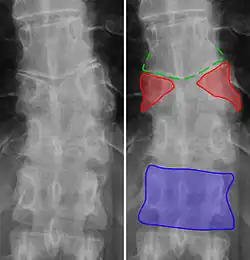

-

Butterfly vertebra (red). Normal vertebra for comparison (blue). -